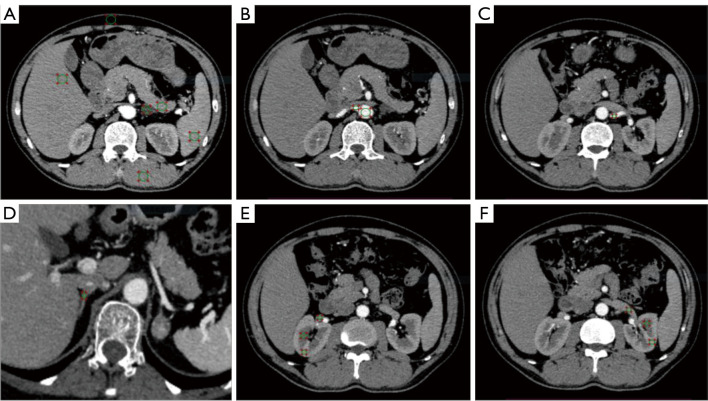

{"title":"肾上腺腺瘤表征的双层光谱检测器计算机断层扫描:辐射剂量减少和多相虚拟非对比成像与真实非对比成像的定量一致。","authors":"Deying Wen, Wen Li, Ling Zhao, Qinglin Du, Xiaoyu Tong, Ailin Liang, Tengxin Wang, Zheng Li, Xiaodi Zhang, Haiwei Liu, Yan Ren, Jiayu Sun","doi":"10.21037/qims-2025-854","DOIUrl":null,"url":null,"abstract":"<p><strong>Background: </strong>Computed tomography (CT) is the preferred imaging modality for evaluating adrenal lesions; however, the associated radiation exposure remains a significant concern. Dual-layer spectral detector CT (SDCT)-derived virtual noncontrast (VNC) images may reduce radiation exposure by eliminating dedicated noncontrast scans, yet their agreement with true noncontrast (TNC) imaging remains debated. This study aimed to quantitatively evaluate the agreement and image quality of VNC images [reconstructed from the arterial phase (VNCa) and portal venous phase (VNCp)] compared to TNC images in adrenal adenomas stratified by lipid content, and to assess the radiation dose reduction.</p><p><strong>Methods: </strong>A total of 103 patients with adrenal adenomas treated at the Adrenal Disease Center of West China Hospital of Sichuan University between March 2023 and September 2024 were enrolled in this prospective study. All patients underwent dual-layer SDCT examination, including TNC and arterial and venous phase scans. VNC images were reconstructed from contrast-enhanced phases. Objective metrics, including CT attenuation value [Hounsfield units (HU)], noise (standard deviation), signal-to-noise ratio (SNR), contrast-to-noise ratio, and absolute attenuation error, and subjective image quality were compared. Interobserver agreement was assessed through the calculation of interclass correlation coefficients. For objective and subjective comparisons between TNC and VNC images, statistical analyses were performed with paired <i>t</i>-tests and Wilcoxon signed-rank tests. The radiation dose with and without TNC was calculated.</p><p><strong>Results: </strong>This study included 103 patients (48 males and 55 females) with a mean age of 51.33±12.55 years. A total of 123 adrenal adenomas were identified, including 28 lipid-rich adenomas and 95 lipid-poor adenomas. For lipid-poor adenomas, VNC and TNC images showed excellent agreement in CT attenuation values (P>0.05), and compared to VNCp images, VNCa images exhibited significantly lower noise (17.44±3.39 <i>vs.</i> 18.64±2.91 HU; P<0.001) and higher SNR (1.68±0.76 <i>vs.</i> 1.55±0.67; P<0.001). In lipid-rich adenomas, VNC images overestimated CT attenuation, showing high absolute attenuation errors (VNCaerror: 9.92±6.49 HU; VNCperror: 8.50±5.17 HU), although these remained within the acceptable threshold of ≤10 HU. In the subjective scores of image quality, TNC images outperformed VNC images [TNC: median 5, interquartile range (IQR) 5-5; VNC: median 5 (IQR 4-5); P<0.001], although VNC scores remained high. No significant statistical difference was observed between the VNCa and VNCp scores (P>0.05). For most of the surrounding nonadenoma tissues, VNC and TNC images demonstrated good agreement, with attenuation differences consistently within ≤10 HU. Replacing TNC images with VNCa images could reduce the effective dose by approximately 32.63% for lipid-poor adenomas.</p><p><strong>Conclusions: </strong>Our findings suggest that for lipid-poor adenomas, VNCa demonstrates high agreement with TNC and provides superior image quality, supporting its use as a TNC substitute for reduced radiation dose. For lipid-rich adenomas, VNC should be applied with caution due to the potential risk of attenuation overestimation. Subtype classification remains essential in such studies.</p>","PeriodicalId":54267,"journal":{"name":"Quantitative Imaging in Medicine and Surgery","volume":"15 9","pages":"7935-7950"},"PeriodicalIF":2.3000,"publicationDate":"2025-09-01","publicationTypes":"Journal Article","fieldsOfStudy":null,"isOpenAccess":false,"openAccessPdf":"https://www.ncbi.nlm.nih.gov/pmc/articles/PMC12397641/pdf/","citationCount":"0","resultStr":"{\"title\":\"Dual-layer spectral detector computed tomography for adrenal adenoma characterization: radiation dose reduction and quantitative agreement of multiphase virtual noncontrast with true noncontrast imaging.\",\"authors\":\"Deying Wen, Wen Li, Ling Zhao, Qinglin Du, Xiaoyu Tong, Ailin Liang, Tengxin Wang, Zheng Li, Xiaodi Zhang, Haiwei Liu, Yan Ren, Jiayu Sun\",\"doi\":\"10.21037/qims-2025-854\",\"DOIUrl\":null,\"url\":null,\"abstract\":\"<p><strong>Background: </strong>Computed tomography (CT) is the preferred imaging modality for evaluating adrenal lesions; however, the associated radiation exposure remains a significant concern. Dual-layer spectral detector CT (SDCT)-derived virtual noncontrast (VNC) images may reduce radiation exposure by eliminating dedicated noncontrast scans, yet their agreement with true noncontrast (TNC) imaging remains debated. This study aimed to quantitatively evaluate the agreement and image quality of VNC images [reconstructed from the arterial phase (VNCa) and portal venous phase (VNCp)] compared to TNC images in adrenal adenomas stratified by lipid content, and to assess the radiation dose reduction.</p><p><strong>Methods: </strong>A total of 103 patients with adrenal adenomas treated at the Adrenal Disease Center of West China Hospital of Sichuan University between March 2023 and September 2024 were enrolled in this prospective study. All patients underwent dual-layer SDCT examination, including TNC and arterial and venous phase scans. VNC images were reconstructed from contrast-enhanced phases. Objective metrics, including CT attenuation value [Hounsfield units (HU)], noise (standard deviation), signal-to-noise ratio (SNR), contrast-to-noise ratio, and absolute attenuation error, and subjective image quality were compared. Interobserver agreement was assessed through the calculation of interclass correlation coefficients. For objective and subjective comparisons between TNC and VNC images, statistical analyses were performed with paired <i>t</i>-tests and Wilcoxon signed-rank tests. The radiation dose with and without TNC was calculated.</p><p><strong>Results: </strong>This study included 103 patients (48 males and 55 females) with a mean age of 51.33±12.55 years. A total of 123 adrenal adenomas were identified, including 28 lipid-rich adenomas and 95 lipid-poor adenomas. For lipid-poor adenomas, VNC and TNC images showed excellent agreement in CT attenuation values (P>0.05), and compared to VNCp images, VNCa images exhibited significantly lower noise (17.44±3.39 <i>vs.</i> 18.64±2.91 HU; P<0.001) and higher SNR (1.68±0.76 <i>vs.</i> 1.55±0.67; P<0.001). In lipid-rich adenomas, VNC images overestimated CT attenuation, showing high absolute attenuation errors (VNCaerror: 9.92±6.49 HU; VNCperror: 8.50±5.17 HU), although these remained within the acceptable threshold of ≤10 HU. In the subjective scores of image quality, TNC images outperformed VNC images [TNC: median 5, interquartile range (IQR) 5-5; VNC: median 5 (IQR 4-5); P<0.001], although VNC scores remained high. No significant statistical difference was observed between the VNCa and VNCp scores (P>0.05). For most of the surrounding nonadenoma tissues, VNC and TNC images demonstrated good agreement, with attenuation differences consistently within ≤10 HU. Replacing TNC images with VNCa images could reduce the effective dose by approximately 32.63% for lipid-poor adenomas.</p><p><strong>Conclusions: </strong>Our findings suggest that for lipid-poor adenomas, VNCa demonstrates high agreement with TNC and provides superior image quality, supporting its use as a TNC substitute for reduced radiation dose. For lipid-rich adenomas, VNC should be applied with caution due to the potential risk of attenuation overestimation. Subtype classification remains essential in such studies.</p>\",\"PeriodicalId\":54267,\"journal\":{\"name\":\"Quantitative Imaging in Medicine and Surgery\",\"volume\":\"15 9\",\"pages\":\"7935-7950\"},\"PeriodicalIF\":2.3000,\"publicationDate\":\"2025-09-01\",\"publicationTypes\":\"Journal Article\",\"fieldsOfStudy\":null,\"isOpenAccess\":false,\"openAccessPdf\":\"https://www.ncbi.nlm.nih.gov/pmc/articles/PMC12397641/pdf/\",\"citationCount\":\"0\",\"resultStr\":null,\"platform\":\"Semanticscholar\",\"paperid\":null,\"PeriodicalName\":\"Quantitative Imaging in Medicine and Surgery\",\"FirstCategoryId\":\"3\",\"ListUrlMain\":\"https://doi.org/10.21037/qims-2025-854\",\"RegionNum\":2,\"RegionCategory\":\"医学\",\"ArticlePicture\":[],\"TitleCN\":null,\"AbstractTextCN\":null,\"PMCID\":null,\"EPubDate\":\"2025/8/14 0:00:00\",\"PubModel\":\"Epub\",\"JCR\":\"Q2\",\"JCRName\":\"RADIOLOGY, NUCLEAR MEDICINE & MEDICAL IMAGING\",\"Score\":null,\"Total\":0}","platform":"Semanticscholar","paperid":null,"PeriodicalName":"Quantitative Imaging in Medicine and Surgery","FirstCategoryId":"3","ListUrlMain":"https://doi.org/10.21037/qims-2025-854","RegionNum":2,"RegionCategory":"医学","ArticlePicture":[],"TitleCN":null,"AbstractTextCN":null,"PMCID":null,"EPubDate":"2025/8/14 0:00:00","PubModel":"Epub","JCR":"Q2","JCRName":"RADIOLOGY, NUCLEAR MEDICINE & MEDICAL IMAGING","Score":null,"Total":0}

背景:计算机断层扫描(CT)是评估肾上腺病变的首选成像方式;然而,相关的辐射暴露仍然是一个重大问题。双层光谱探测器CT (SDCT)衍生的虚拟非对比(VNC)图像可以通过消除专用的非对比扫描来减少辐射暴露,但它们与真正的非对比(TNC)成像的一致性仍存在争议。本研究旨在定量评价按脂质含量分层的肾上腺腺瘤的VNC图像[由动脉期(VNCa)和门静脉期(VNCp)重建]与TNC图像的一致性和图像质量,并评估辐射剂量的减少。方法:本前瞻性研究纳入2023年3月至2024年9月在四川大学华西医院肾上腺疾病中心接受治疗的肾上腺腺瘤患者103例。所有患者均行双层SDCT检查,包括TNC期和动、静脉期扫描。从对比度增强阶段重建VNC图像。比较客观指标,包括CT衰减值[Hounsfield units (HU)]、噪声(标准差)、信噪比(SNR)、对比噪声比、绝对衰减误差,以及主观图像质量。通过计算类间相关系数来评估观察者间的一致性。对于TNC和VNC图像的客观和主观比较,采用配对t检验和Wilcoxon符号秩检验进行统计分析。计算了有无TNC的辐射剂量。结果:103例患者(男48例,女55例),平均年龄51.33±12.55岁。共发现123例肾上腺腺瘤,其中富脂腺瘤28例,贫脂腺瘤95例。对于低脂腺瘤,VNC与TNC影像在CT衰减值上表现出极好的一致性(P < 0.05),且与VNCp影像相比,VNCa影像表现出更低的噪声(17.44±3.39 vs. 18.64±2.91 HU; Pvs. 1.55±0.67;P0.05)。对于大多数周围非腺瘤组织,VNC和TNC图像表现出良好的一致性,衰减差异在≤10 HU范围内一致。对于脂质贫乏的腺瘤,用VNCa图像代替TNC图像可使有效剂量降低约32.63%。结论:我们的研究结果表明,对于脂质贫乏的腺瘤,VNCa与TNC表现出高度的一致性,并提供了优越的图像质量,支持其作为TNC替代降低辐射剂量。对于富含脂质的腺瘤,VNC应用应谨慎,因为衰减高估的潜在风险。亚型分类在这类研究中仍然是必不可少的。

Methods: A total of 103 patients with adrenal adenomas treated at the Adrenal Disease Center of West China Hospital of Sichuan University between March 2023 and September 2024 were enrolled in this prospective study. All patients underwent dual-layer SDCT examination, including TNC and arterial and venous phase scans. VNC images were reconstructed from contrast-enhanced phases. Objective metrics, including CT attenuation value [Hounsfield units (HU)], noise (standard deviation), signal-to-noise ratio (SNR), contrast-to-noise ratio, and absolute attenuation error, and subjective image quality were compared. Interobserver agreement was assessed through the calculation of interclass correlation coefficients. For objective and subjective comparisons between TNC and VNC images, statistical analyses were performed with paired t-tests and Wilcoxon signed-rank tests. The radiation dose with and without TNC was calculated.

Results: This study included 103 patients (48 males and 55 females) with a mean age of 51.33±12.55 years. A total of 123 adrenal adenomas were identified, including 28 lipid-rich adenomas and 95 lipid-poor adenomas. For lipid-poor adenomas, VNC and TNC images showed excellent agreement in CT attenuation values (P>0.05), and compared to VNCp images, VNCa images exhibited significantly lower noise (17.44±3.39 vs. 18.64±2.91 HU; P<0.001) and higher SNR (1.68±0.76 vs. 1.55±0.67; P<0.001). In lipid-rich adenomas, VNC images overestimated CT attenuation, showing high absolute attenuation errors (VNCaerror: 9.92±6.49 HU; VNCperror: 8.50±5.17 HU), although these remained within the acceptable threshold of ≤10 HU. In the subjective scores of image quality, TNC images outperformed VNC images [TNC: median 5, interquartile range (IQR) 5-5; VNC: median 5 (IQR 4-5); P<0.001], although VNC scores remained high. No significant statistical difference was observed between the VNCa and VNCp scores (P>0.05). For most of the surrounding nonadenoma tissues, VNC and TNC images demonstrated good agreement, with attenuation differences consistently within ≤10 HU. Replacing TNC images with VNCa images could reduce the effective dose by approximately 32.63% for lipid-poor adenomas.